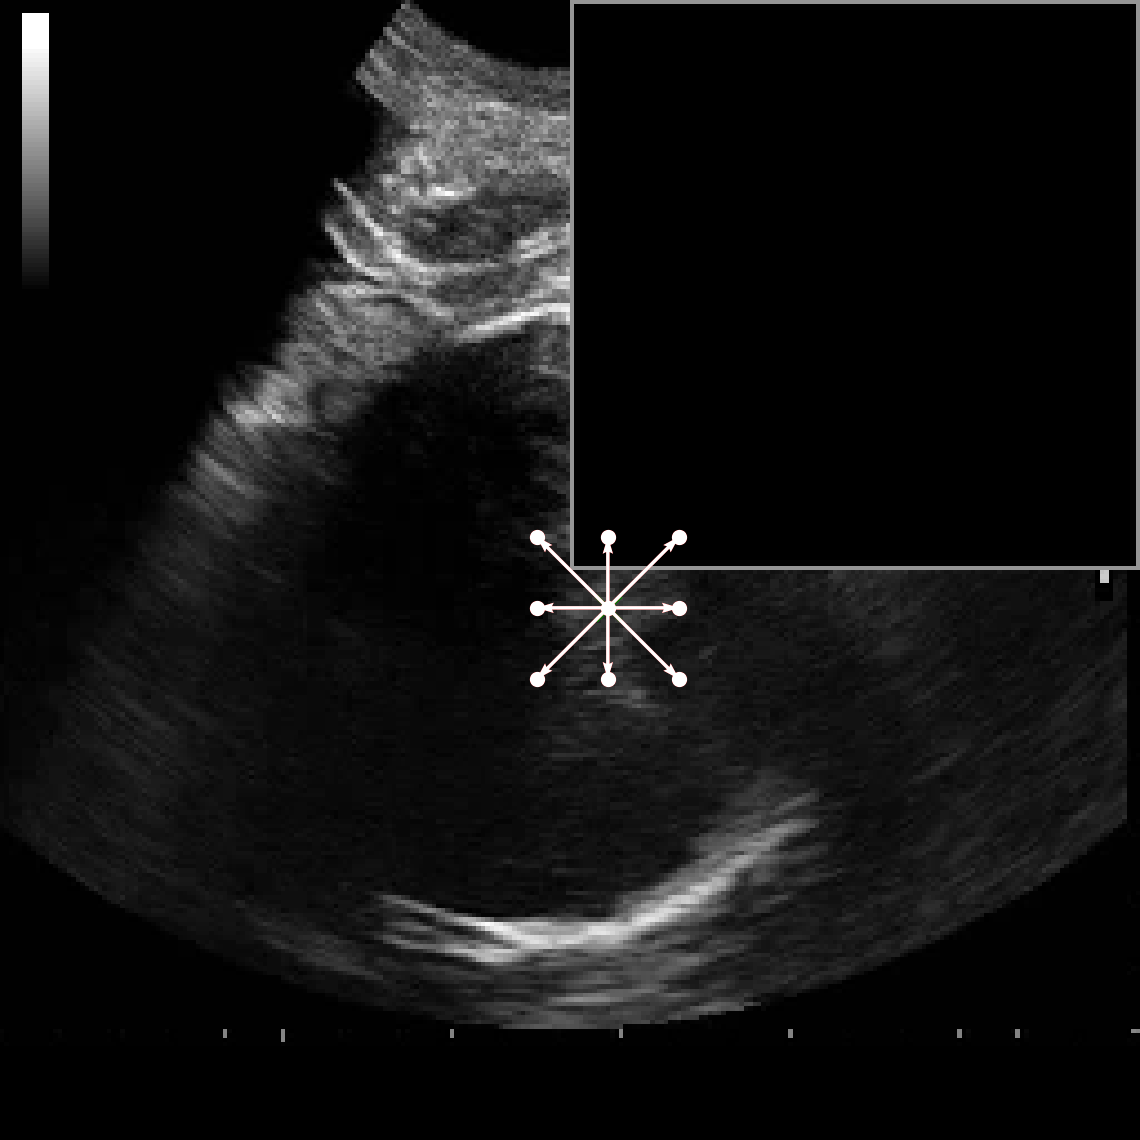

In practical clinical settings, medical images are often incomplete or degraded due to occlusions, artifacts, or limited fields-of-view. Therefore, a reliable segmentation model must be robust to missing spatial context and capable of inferring anatomical structures from partially observed inputs. To evaluate this critical property, we conducted a masking experiment using the FH-PS-AoP dataset. In this experiment, we systematically removed one quadrant from the input image, top-left, top-right, bottom-left, or bottom-right, and evaluated the performance of DAUNet compared to the baseline UNet.

Figure 7 presents a comprehensive visual comparison of the predicted offset maps and segmentation masks under each masking condition. The first column shows the original (unmasked) input along with its corresponding predictions, while subsequent columns depict the results for each of the masked quadrants.

DAUNet demonstrates markedly higher resilience to missing context compared to UNet. Its predicted offset maps remain dense and structured, with vectors that preserve anatomical directionality even when significant regions of the input are absent. This behavior reflects DAUNet’s ability to infer context from the remaining visual cues. In contrast, UNet exhibits sparse or disoriented offsets in the masked scenarios, indicating reduced spatial awareness and compromised localization.

To better understand this phenomenon, we analyzed the receptive fields of both models. For a representative pixel, we visualized its corresponding receptive area contributing to the output. In UNet, the receptive field is fixed and grid-constrained (refer to second row of Figure 7), making it sensitive to occlusions. On the other hand, DAUNet leverages deformable convolutions to dynamically adjust its receptive field based on the visible content. This adaptability is evident in the red and white arrows in the fourth column of Figure 7, where DAUNet modifies its offset patterns to account for the masked input.

The segmentation masks in third and fourth rows of Figure 7, further substantiate these findings. DAUNet consistently produces anatomically plausible segmentations of both the fetal head (green) and pubic symphysis (red), with minimal degradation even under 25% missing input. The output contours remain smooth, accurate, and well-aligned with ground truth boundaries. In contrast, UNet’s performance deteriorates noticeably, with fragmented or distorted segmentations, especially around the fetal head, as indicated by white arrows in the figure.

These results highlight the efficacy of DAUNet’s architectural innovations. The combination of deformable convolution and SimAM attention allows the model to effectively reason over the visible context and compensate for spatial omissions. This robustness to incomplete inputs makes DAUNet well-suited for deployment in real-world medical environments, where noise, occlusions, and partial data are common challenges.